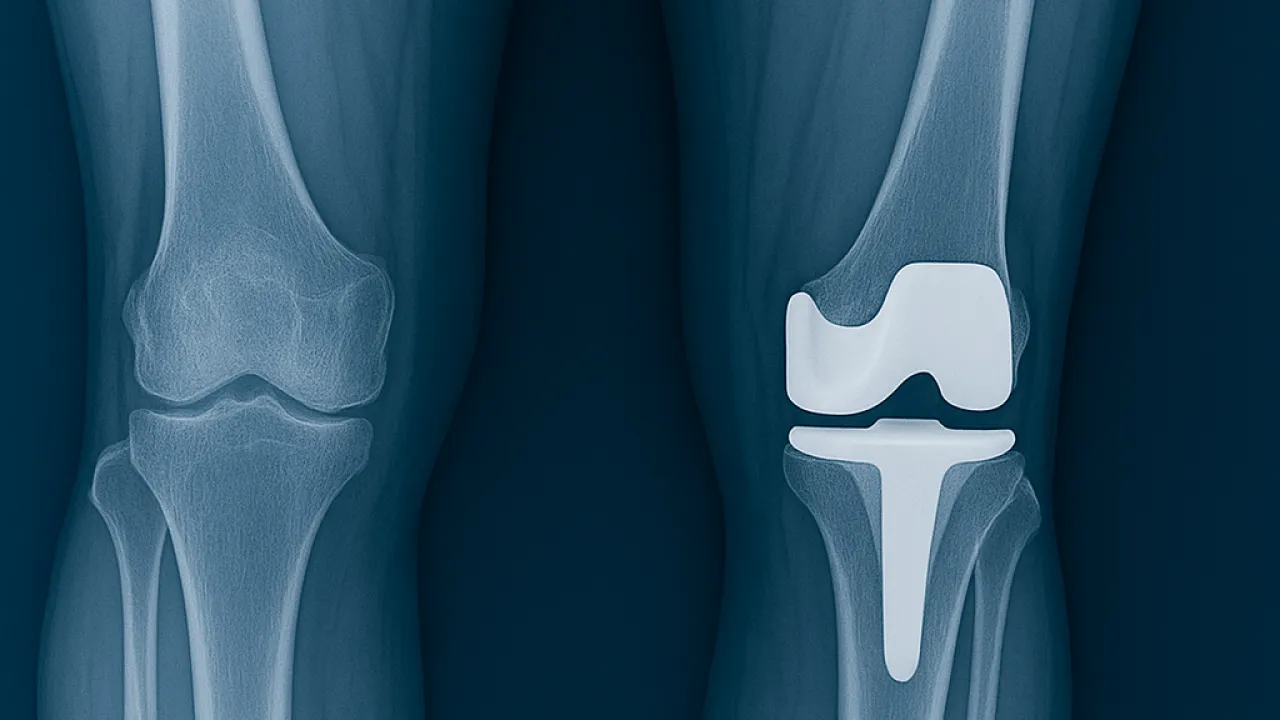

Eklem protez cerrahisi (artroplasti), halk arasında “eklem protezi” olarak bilinir. En çok kireçlenen eklem ve en çok protez uygulanan eklem diz eklemidir. Bunun ardından Kalça eklemi gelir. Ayrıca omuz, ayak bileği ve el bileği eklemlerinde de kireçlenme yani artroz sonrası eklem protez cerrahisi uygulanmaktadır. Eklemlerimiz zamanla yıpranabilir veya kireçlenme nedeniyle görevini yapamaz hale gelebilir. Bunun birçok sebebi vardır. Bu durumda protez cerrahisi sayesinde ağrısız hareket etmek, günlük hayata geri dönmek mümkündür. Türkiye'de protez cerrahisi 90'lı yıllarda İstanbul, İzmir ve Ankara gibi illerde yapılırken şu an her şehirde yapılabilmektedir. Ege Üniversitesi'nde diz protezi ve kalça protezleri konusunda 40 yıllık deneyimi olan Hakkı Sur ile eğitim aldıktan sonra Fransa'da yine ünlü protez merkezinde birçok vakaya katılmış ve yapmış olmanın bu cerrahideki önemini meslek hayatımda daha da idrak ettim.

En sık uygulanan eklem protezleri:

Bu şikayetler ilaç, fizik tedavi ya da enjeksiyon tedavileriyle düzelmiyorsa protez cerrahisi gündeme gelir.

Öncelikle ağrının nedeni belirlenmelidir. Ameliyat dışı tedavilerle ağrı ve işlev kısıtlılığı giderilmeye çalışılır. Tedavi hastalığın erken evrelerinde ilaç (ağrı kesici-analjezik ve ödem çözücü-antienflamatuar) ve fizik tedavi uygulamalarıyla yapılabilir. Hastalara kilo verme ve yerde oturmama öğütlenmelidir. Aslında kireçlenme nispeten erken yaşlarda 40- 50'li yaşlarda başlar. Birçok hasta hayat şartları ve diğer sebeplerle bize geç başvurabilmektedir. Daha erken dönemde başvuran hastalarda PRP, EKSOSOM ve KÖK HÜCRE tedavileriyle kireçlenme durdurulabilmektedir. Bunun dışında diz içi enjeksiyonları (diz sıvıları) hyaluronik asit yapılabilmektedir.

Klinik uygulamada protez olan hasta ameliyat sonrası ilk günde ayağa kaldırılmaktadır. Yatak içi ve yatak kenarında fizik tedavi hareketleri yapılmaktadır. 2. gün hastanın hareket açıklığı artırılmaktadır. 3. günde ise fizyoterapistler eşliğinde merdiven inip çıkma egzersizleri öğretilmektedir. Hasta evine giderken sondası çıkmış ve tuvalete gidebilecek şekilde plan yapmaktayız. Dikişler için 15 gün sonra kontrole gelen hasta tekrar değerlendirilmektedir.

Artroplasti cerrahisine aday olan hastalarda yaşla birlikte eşlik eden hastalıklar anestezi ve cerrahi için riskler oluşturmaktadır. Enfeksiyon (iltihaplanma), toplardamarlarda pıhtı oluşumu ve proteze ait sorunlar önemli sorunlar olarak dikkat çekmektedir.

Proteze bağlı mekanik sorunlar (protezin çıkması, aşınma, gevşeme) günümüzde daha nadir görülen sorunlardandır. Bunlar ise cerrahın deneyimine ve protezin kalitesine bağlıdır. Kaliteli protez ve deneyimli cerrah protez ömrünün 20 yıl ve üzerine çıkarmaktadır.